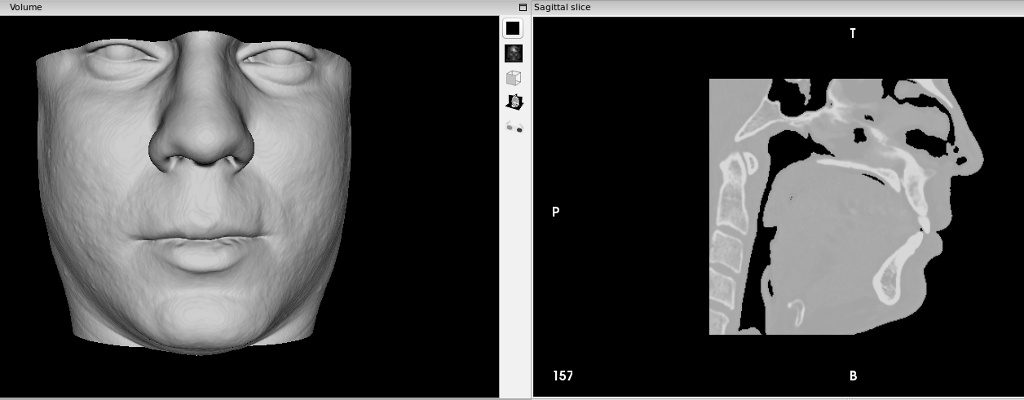

Программа InVesalius — для реконструкции 3D из DICOM снимков. Достаточно простая в использовании и не столь многофункциональна как 3D slicer. Но зато быстро позволяет добиться результата. Так я получил 3D модель лицевой части, повращал свой череп во вьюпорте и воскликнул «бедный Йорик!».

3D slicer намного более функциональный пакет чем InVesalius. 3D slicer для ученых-медиков, как Blender для 3D графики. Функциональный, но надо потратить время на изучение. У меня нет столько свободного времени и желания углубляться в этот софт. Лучше я продолжу писать статьи про аспектно-ориентированное программирование, а эти программы оставлю студентам-медикам и ученым. Для меня стало неожиданностью что столько медицинских программ есть в open source!!!

Ручной процесс сегментирование изображения 36 зуба на КТ в InVesalius очень напоминает процесс создания маски кистью в растровом редакторе.

Автоматическое сегментирование изображения захватывало все костные ткани в изображениях и поэтому не подошло. Если интересно чтобы записал скринкаст процесса создания модели, пишите в комментариях.

В завершении этой фотосессии, сделал 3D модель коронковой части 36 зуба после сегментации вручную срезов томографии.

После лечения зуба за свой счет- это тот же объем что и на фото выше. Интерфейс InVesalius

Интересно, удавалось ли другим пациентам в такой ситуации доказать реальную степень разрушения зуба. Делает ли какая-либо клиника такую экспертизу? Теоретически, модель зуба может быть объективным аргументом в споре со страховой. По-моему отличная тема для диссертации стоматолога!!!